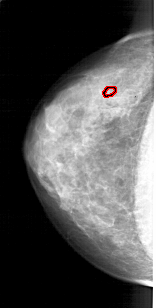

A_1914_1.LEFT_CC

LEFT_CC LINES 4306 PIXELS_PER_LINE 2176 BITS_PER_PIXEL 12 RESOLUTION 43.5 OVERLAY

FILE: A_1914_1.LEFT_CC.OVERLAY

TOTAL_ABNORMALITIES 1

ABNORMALITY 1

LESION_TYPE CALCIFICATION TYPE PLEOMORPHIC DISTRIBUTION CLUSTERED

ASSESSMENT 4

SUBTLETY 2

PATHOLOGY BENIGN

TOTAL_OUTLINES 1